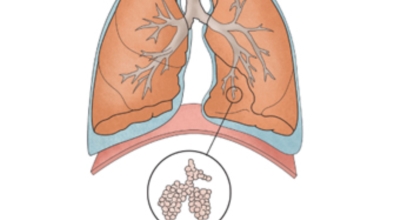

폐암 환자의 1/4에서 나타나는 공통적인 증상으로 호흡곤란이 일어나는 이유는 다발성 폐전이가 폐 양쪽에서 발견되는 경우 발생할 수 있으며 폐암과 또한 악성 흉수가 동반되는 경우 발생합니다. 평소와 다르게 숨이 차는 느낌이 들면서 숨을 들이쉬고 내쉴때 쌕쌕 거리는 소리나 나온다면 폐암 증상을 의심해 볼 수 있어요.

악성 종양이 있는 폐의 일부를 절제하는 방법입니다. 초기에는 내시경 기구를 이용하여 수술이 가능하기도 합니다.

항암제를 이용한 치료 방법입니다. 폐암 4기 같은 경우에는 항암 화학요법이 유일한 치료방법이기도 합니다. 폐암에 대해서 알아봤는데요.